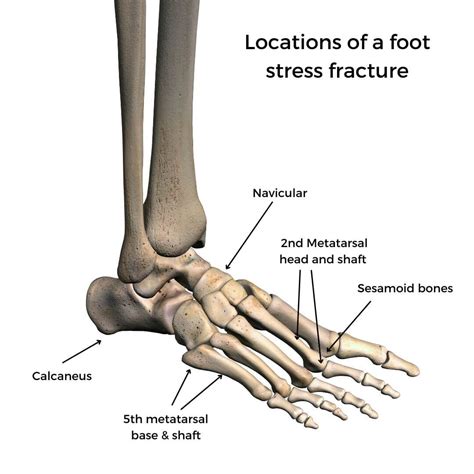

Understanding Stress Fractures

A stress fracture is a small crack in a bone caused by repetitive force, often from overuse. Unlike acute fractures resulting from a single traumatic event, stress fractures develop gradually. The heel bone, or calcaneus, is particularly susceptible to stress fractures due to the significant weight and pressure it bears during daily activities.

Causes of Stress Fracture Heel

Several factors contribute to the development of a stress fracture heel. Understanding these causes can help in prevention and early intervention: